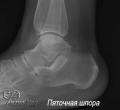

Как лечить пяточную шпору?

По словам специалистов, нарушение характера походки в 93% случаев заметно при пяточной шпоре. При слишком интенсивных нагрузках и занятия спортом заболевание провоцируют нагрузки на стопы. Боли бывают острыми, жгучими. При появлении шпор на пятках ст...